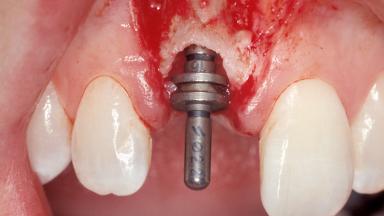

A 30-year-old female patient was referred to the office for the treatment of tooth 11. Her chief concern at the initial visit was to inquire, “Why is my tooth pink?” Upon clinical examination, it was determined that tooth 11 had a previous history of trauma and that the clinical crown had become noticeably pink in color as a result of internal resorption. This diagnosis was confirmed radiographically, indicating a large radiolucency involving the central and distal portions of the clinical crown. It was determined that restoration of this tooth was not possible, and that extraction was indicated. The presence of a mid-line diastema, which the patient wanted to reproduce, directed the treatment plan for tooth replacement utilizing a dental implant.